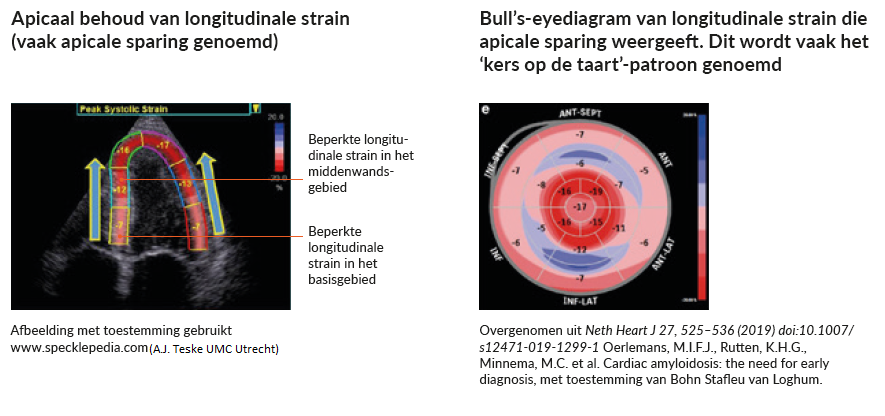

Verminderde longitudinale strain is een andere aanwijzing op de echo die het vermoeden dat uw patiënt cardiale amyloïdose heeft, kan doen toenemen. Hierbij gaat het om een longitudinale strain die verminderd is in het basis- en middenwandsgebied. Terwijl de strain in de apex vaak wordt gespaard of behouden blijft wat resulteert in de kenmerkende ‘kers op de taart’, zoals u in onderstaand figuur ziet. 8,10,11

Figuur 2: Voorbeelden van ECHO strain imaging die apicaal behoud weergeven.